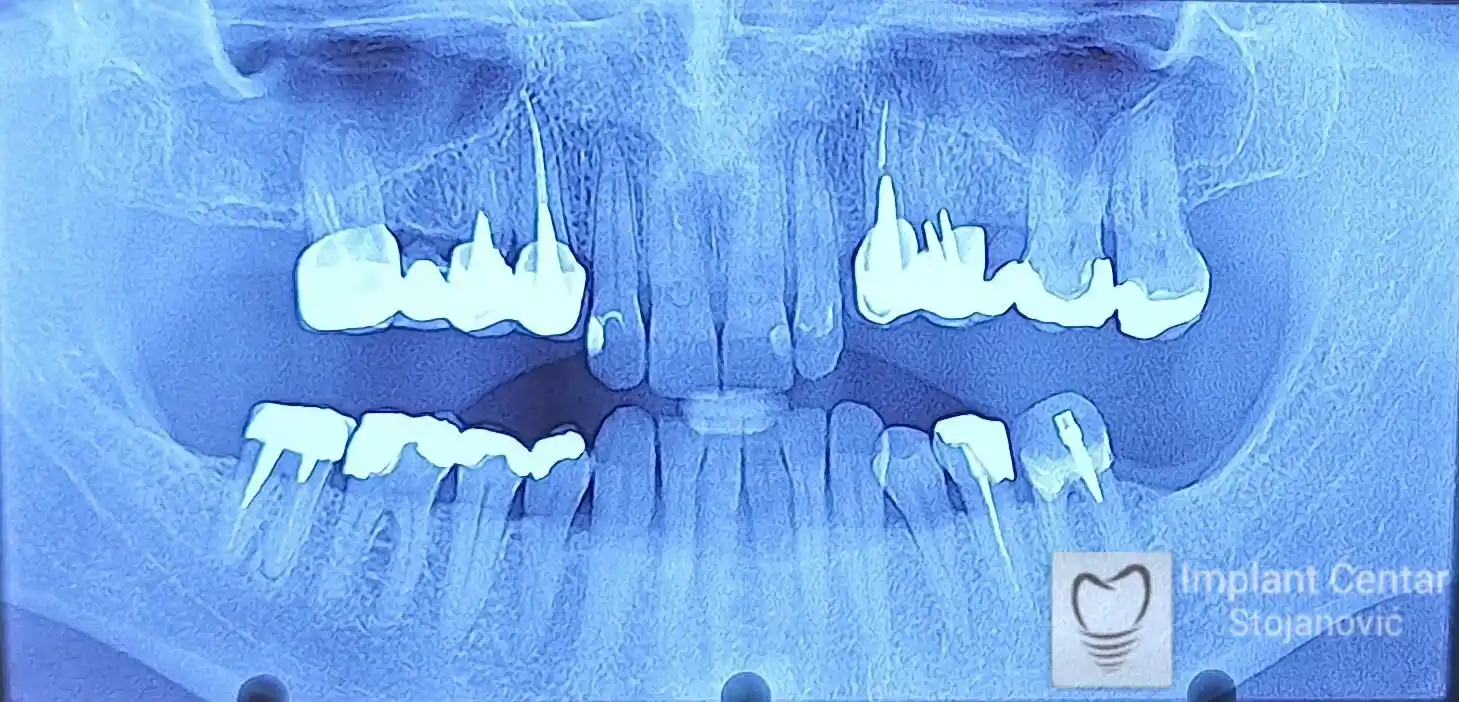

Na slici 1. i slici 2. prikazan je izgled pacijenta pre početka terapije – klinički i rendgenološki.

Nakon vađenja zuba, ugrađeni su implantati. Na slici 3 prikazan je ortopan snimak sa ugrđenim implantatima. Tokom perioda osteointegracije, pacijent je bio zbrinut fiksnim privremenim krunicama na implantatima, koje su izrađene samo dva dana nakon hirurške intervencije.

Na slikama 5. i 6. prikazan je izgled definitivnih cirkonijum-keramičkih mostova na implantatima.